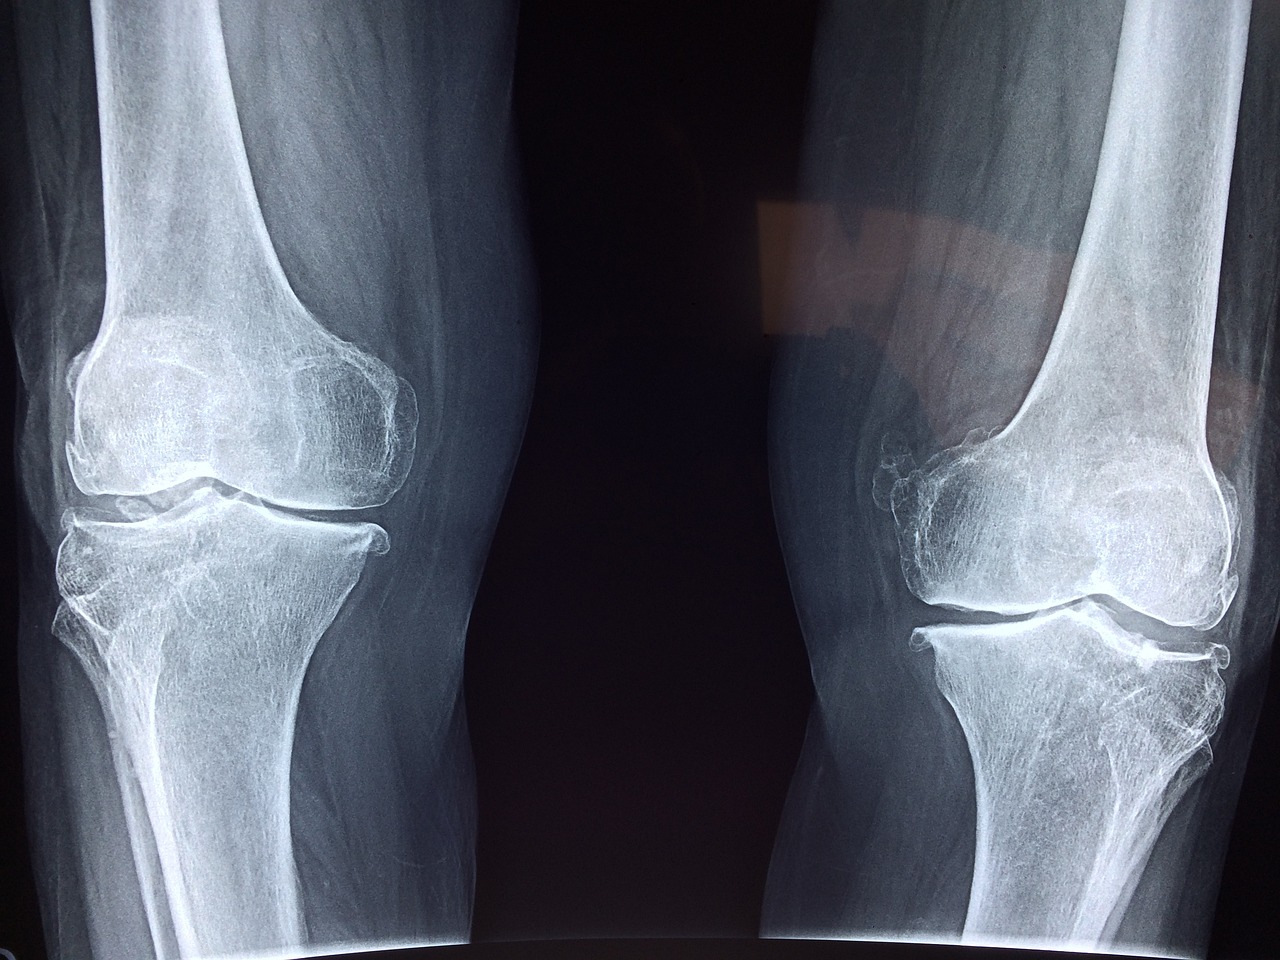

골다공증은 뼈의 밀도가 감소하고 구조가 약해져서 뼈가 쉽게 부러지는 질환입니다. 이 질환의 주요 원인은 여러 가지가 있으며, 그중 가장 일반적인 원인은 나이입니다. 나이가 들면서 뼈의 재생 속도가 감소하고, 뼈의 밀도가 자연스럽게 줄어들게 됩니다. 특히 여성의 경우, 폐경 후 에스트로겐 수치가 급격히 감소하면서 골밀도가 빠르게 감소할 수 있습니다. 또한, 유전적인 요인도 골다공증의 중요한 원인 중 하나입니다. 가족력이 있는 경우, 골다공증에 걸릴 확률이 높아질 수 있습니다. 이 외에도 생활 습관 요인들이 골다공증의 발병에 큰 영향을 미칩니다. 예를 들어, 칼슘과 비타민 D가 부족한 식단은 뼈 건강에 부정적인 영향을 미칠 수 있습니다. 칼슘은 뼈의 주요 구성 요소이며, 비타민 D는 칼슘의 흡수를 돕기 때문에 이 두 가지 영양소가 부족하면 뼈가 약해질 수 있습니다. 흡연과 과도한 음주도 골다공증의 위험을 증가시키는 요인입니다. 흡연은 뼈의 혈액 공급을 감소시키고, 알코올은 뼈의 형성을 방해할 수 있습니다. 또한, 운동 부족은 뼈를 약하게 만들 수 있습니다. 규칙적인 체중 부하 운동은 뼈를 강화하는 데 도움이 되므로, 운동이 부족한 생활은 골다공증의 위험을 높일 수 있습니다. 호르몬 불균형 또한 골다공증의 원인 중 하나로, 특히 갑상선 호르몬의 과잉은 뼈 손실을 가속화할 수 있습니다. 일부 약물, 특히 스테로이드 계열의 약물은 장기 복용 시 골다공증의 위험을 증가시킬 수 있습니다. 마지막으로, 특정 질환도 골다공증과 연관이 있습니다. 예를 들어, 류머티즘 관절염이나 만성 신장 질환과 같은 질환은 골밀도를 감소시킬 수 있습니다.

골다공증은 초기에는 뚜렷한 증상이 없기 때문에 '조용한 질병'으로 불리기도 합니다. 그러나 시간이 지나면서 뼈가 약해지고 골절의 위험이 증가하게 됩니다. 주요 증상으로는 척추, 고관절, 손목 등에서 발생하는 골절이 있습니다. 특히 척추 골절은 통증을 유발할 수 있으며, 심한 경우에는 자세의 변화나 키가 줄어드는 원인이 될 수 있습니다. 또한, 골절이 발생하지 않더라도 만성적인 허리 통증이나 뼈의 약화로 인해 일상적인 활동에서 불편함을 느낄 수 있습니다. 골다공증으로 인한 골절은 회복이 더디고, 특히 노인의 경우에는 장기적인 이동성 감소와 같은 심각한 결과를 초래할 수 있습니다. 따라서, 아래에서 소개되는 조기 진단과 예방이 매우 중요하며, 뼈의 건강을 유지하기 위한 생활 습관 개선이 필요합니다.